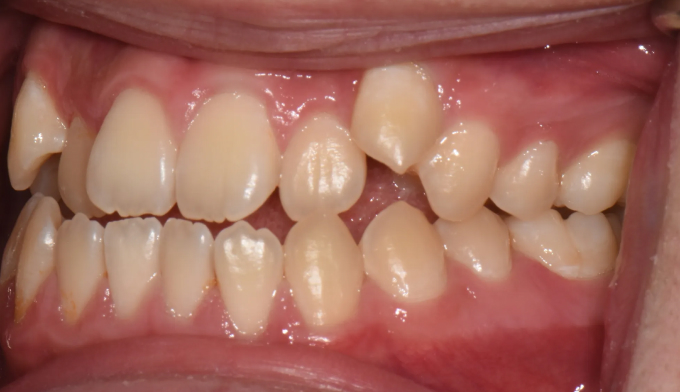

주걱턱 경향을 갖는 청소년들은 개방교합과 덧니를 동시에 갖는 경우가 많습니다. 아래턱의 과도한 성장은 혀의 위치를 아래로 처지게 만들고, 이는 위턱의 폭을 줄어들게 만들어 덧니가 생기기 쉽게 만듭니다. 그리고 과도한 아래턱의 성장은 앞니의 교합을 벌어지게 만들어 개방교합 또한 나타나게 됩니다.

그 정도에 따라 발치가 필요한 경우도 있지만, 성장기의 청소년의 경우에는 최대한 발치 없이 자연스러운 치열과 입매를 만드려고 합니다.

좁아진 위턱 악궁을 확장시켜서 치아를 배열시키고, 과도하게 앞으로 나온 앞니를 미니스크류를 이용하여 후방이동 시킵니다.

총 치료기간은 24개월 소요되었습니다.